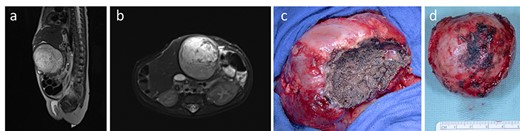

In the following 3 weeks, staged closure was continued without much progress, mostly because of the lesion in the left liver. Work-up of this lesion by ultrasound and MRI demonstrated a 5.5 × 5.1 × 5.5 cm tumor in segment III of the liver consistent with the diagnosis of a vascular tumor. The attempted therapy with propranolol (1 mg/kg/day) was ineffective and was discontinued due to the onset of bradycardia. Finally, surgical resection of the liver tumor was decided. At surgery, the well-defined mass was completely resected (Fig. 2). While the abdominal fascia was closed using a Gore-Tex patch of 3 × 4 cm, the skin was closed directly.

MRI showing the vascularized tumor originating from the liver, occupying the precaval space and protruding outside the abdominal wall level (a, b). At surgery, a cleavage sheet between liver and the mass (c) allowed an easy and complete resection of the tumor (d)

Pathological examination showed a mass enclosed by a capsule of about 2 mm and containing a marginal area rich in a dense network of capillary vessels and a central necrotic region. Immunohistochemical examination was positive for endothelial markers CD31 and CD34, and negative for GLUT1. The proliferation rate under 5% and the sequencing of GNA-11 mutation made the diagnosis of RICH the most appropriate.